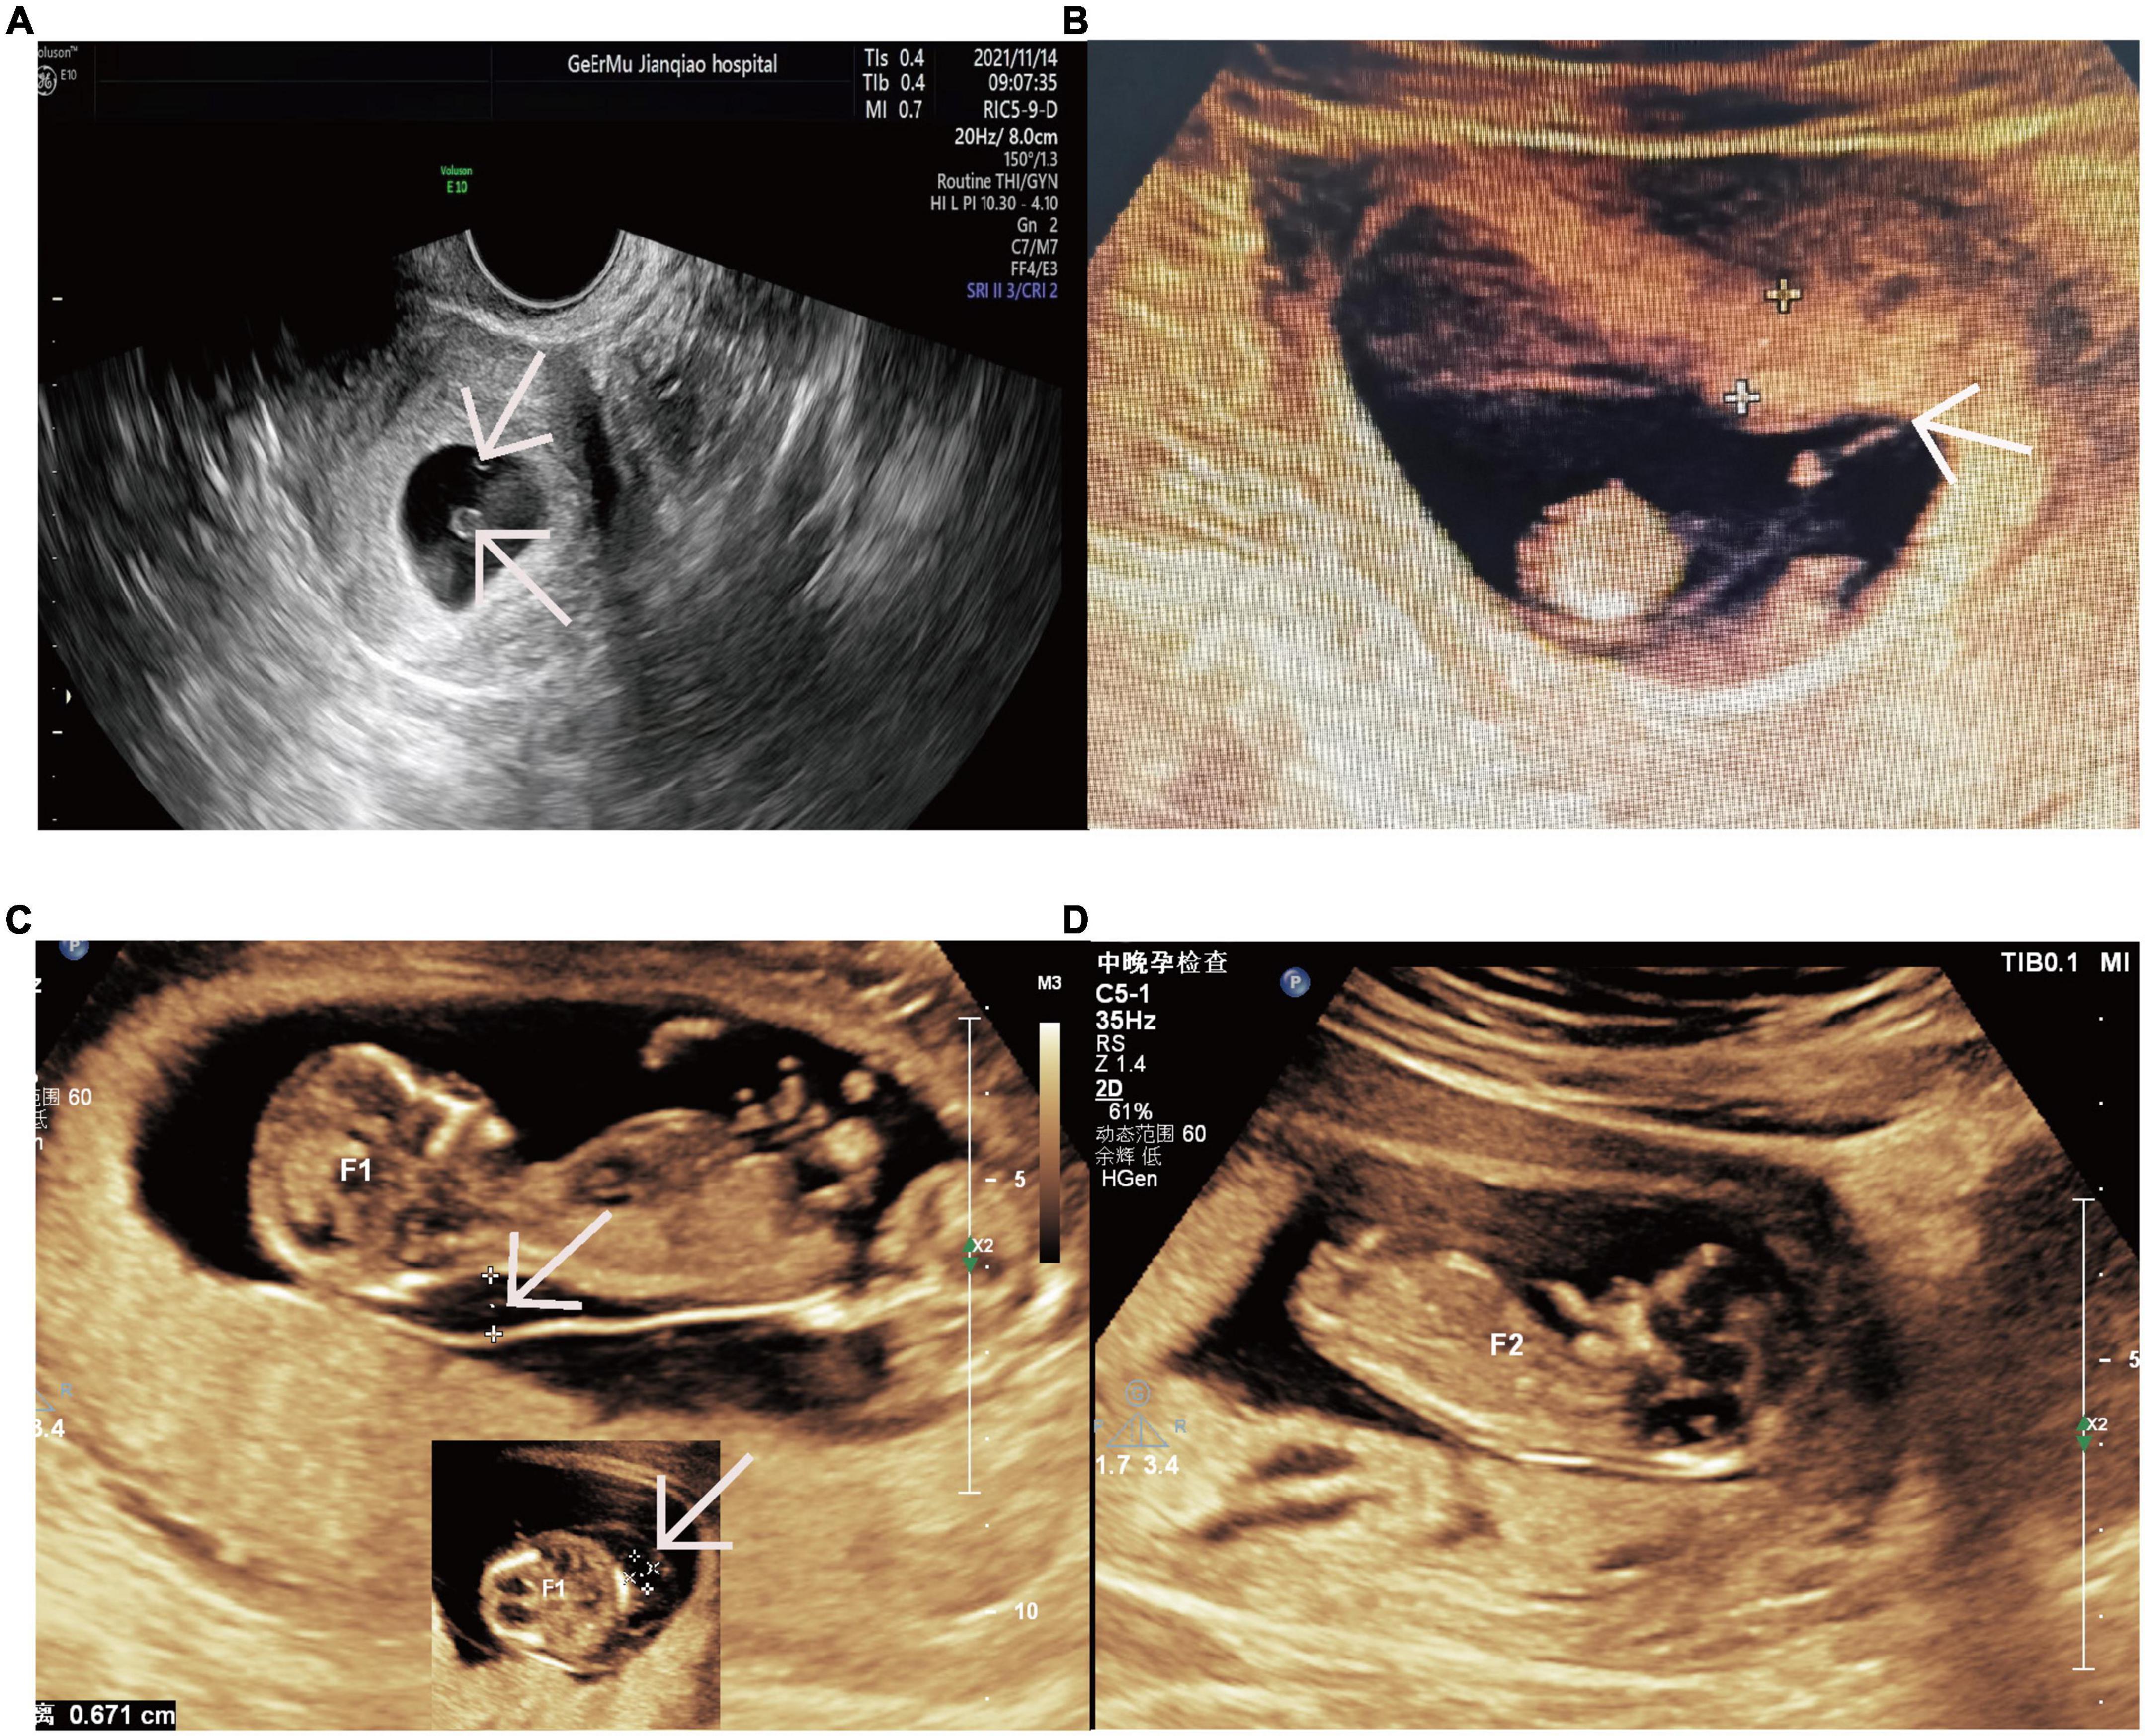

Confused by the IUFD medical abbreviation? Discover what an intrauterine fetal death is, the clinical definitions used by healthcare providers, and the essential diagnostic procedures involved. Our expert guide clarifies the terminology, causes, and supportive care options surrounding this pregnancy loss, helping you navigate complex medical documentation with clear, accurate, and reliable information.